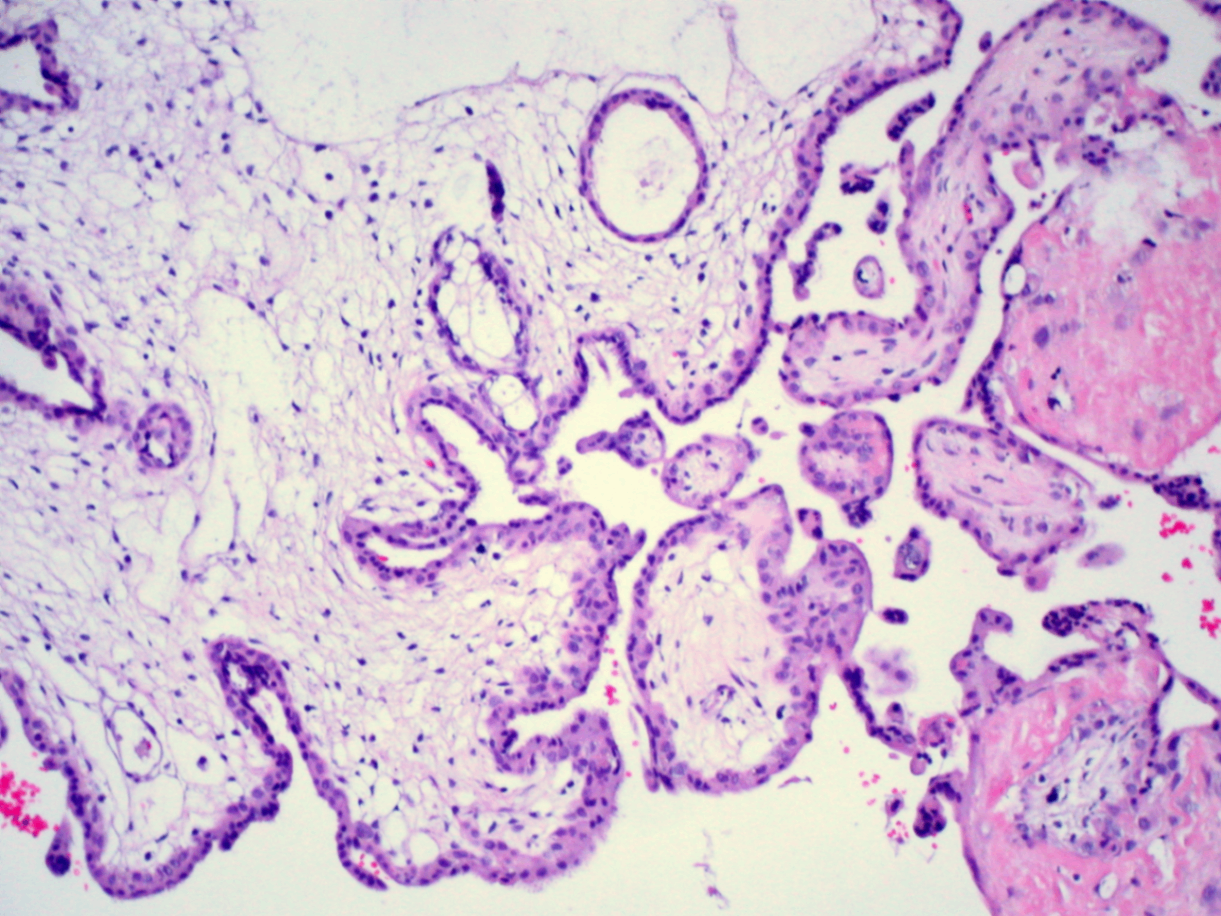

Complete hydatidiform mole, Wikimedia Commons

• 조직학적 형태:

- 전체적으로 edematous (=hydropic swelling), cystic, proliferative 용모막 융모

- 태아 조직 없음